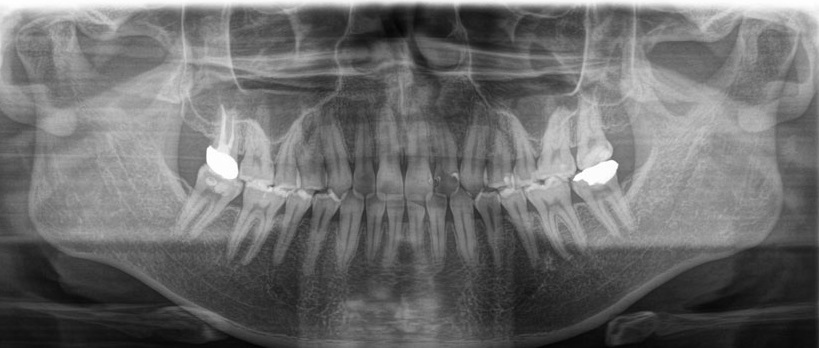

歯周病は顎の骨を溶かす病気ですので、CTやレントゲン検査を行い、顎の骨の状態を確認します。